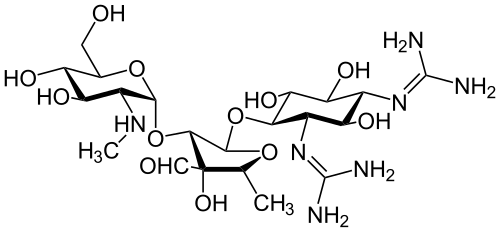

The standard treatment is with a minimum of four weeks of high-dose intravenous penicillin with an aminoglycoside such as gentamicin. The use of high-dose antibiotics is largely based upon animal models.[2]